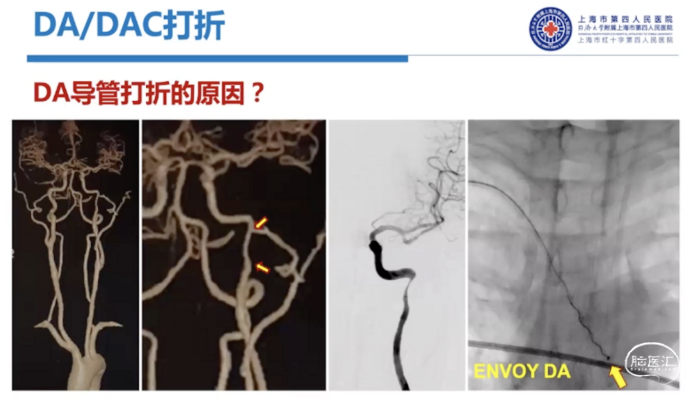

经桡和经股最大的区别:经桡入路,神经介入治疗存在右锁骨下动脉到颈内动脉的反向弯,普通经股入路的导管难以通过,存在打折风险,需要用Sim头端的造影导管进行超选。

现有中间导管/DA导管相对来说都是经股的设计,尤其是中间导管,一般都是要配合长鞘的外支撑来完成。但是经桡的情况下,它的弓部抗折性其实是不够的。这种情况下,我们需要额外的内部支撑。

导管是否打折,和转弯半径有很大关系。一方面取决于导管性能,一方面取决于血管条件。在没有足够支撑情况下,导管非常容易形成锐角,这个时候就容易打折。目前可以通过加硬导丝增加内支撑,让血管在弯的位置更多地靠在大弯一侧,来增加它的半径,进一步减少打折情况的出现。